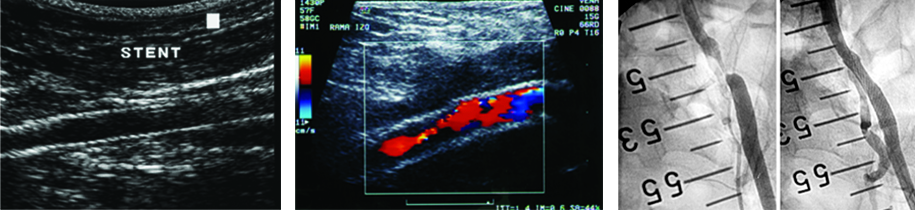

IMÁGENES POSTQUIRÚRGICAS

Realizado el diagnóstico de la arteriopatía, nivel de estenosis y grado de colateralización, el cirujano planteará la cirugía. Es importante para el médico radiólogo saber el tipo de cirugía realizada y el tiempo de evolución de la misma para una correcta interpretación de las imágenes.

De no contar con información sobre el tipo de cirugía realizada, el médico radiólogo llevará a cabo una anamnesis al paciente sobre el tema y la sintomatología actual; asimismo lo examinará en búsqueda de cicatrices que le permitan reconocer la técnica empleada. Luego procederá a evaluar el tipo de injerto y la topografía del bypass, realizará la medición de las velocidades de flujo en las anastomosis y en el injerto, y procederá a medir el índice tobillo-braquial. Identificará el tipo de bypass femoral. Durante el examen se evaluará la velocidad de pico sistólico en el sector de las anastomosis y en el injerto. En el período postquirúrgico el flujo típico es de hiperemia, con diástoles prominentes. Al cabo de dos meses se establece un patrón trifásico típico. La velocidad en el bypass debe ser superior a 40 cm/seg (Fig. 21).

Angioplastia con stent ilíaco

Se utiliza en las estenosis de las arterias ilíacas, su colocación a nivel femoral o poplíteo no tiene buenos resultados a largo plazo, se utilizan en pacientes con alto riesgo quirúrgico10 (Fig. 22).

Complicaciones de los bypass

En estadios precoces se pueden observar bajas velocidades sanguíneas debido a un flujo de entrada o salida insuficiente, por fallas en la anastomosis por problemas intrínsecos del injerto. Los hematomas peri-protésicos son complicaciones frecuentes en el período quirúrgico inmediato (Fig. 23). Dentro del primer año se pueden dar obstrucciones por defectos en la cirugía o por hiperplasia fibrointimal. Luego de los dos años puede darse la progresión de la enfermedad en los vasos nativos proximales y distales al bypass. La complicación más tardía, de 5 a 10 años, es el desarrollo de pseudo-aneurismas en el lugar de las anastomosis distales.

Pseudo-aneurisma

Complicación tardía de las anastomosis de los bypass, también pueden presentarse por traumatismo en la anastomosis, como se observa en la imagen (Fig. 24).